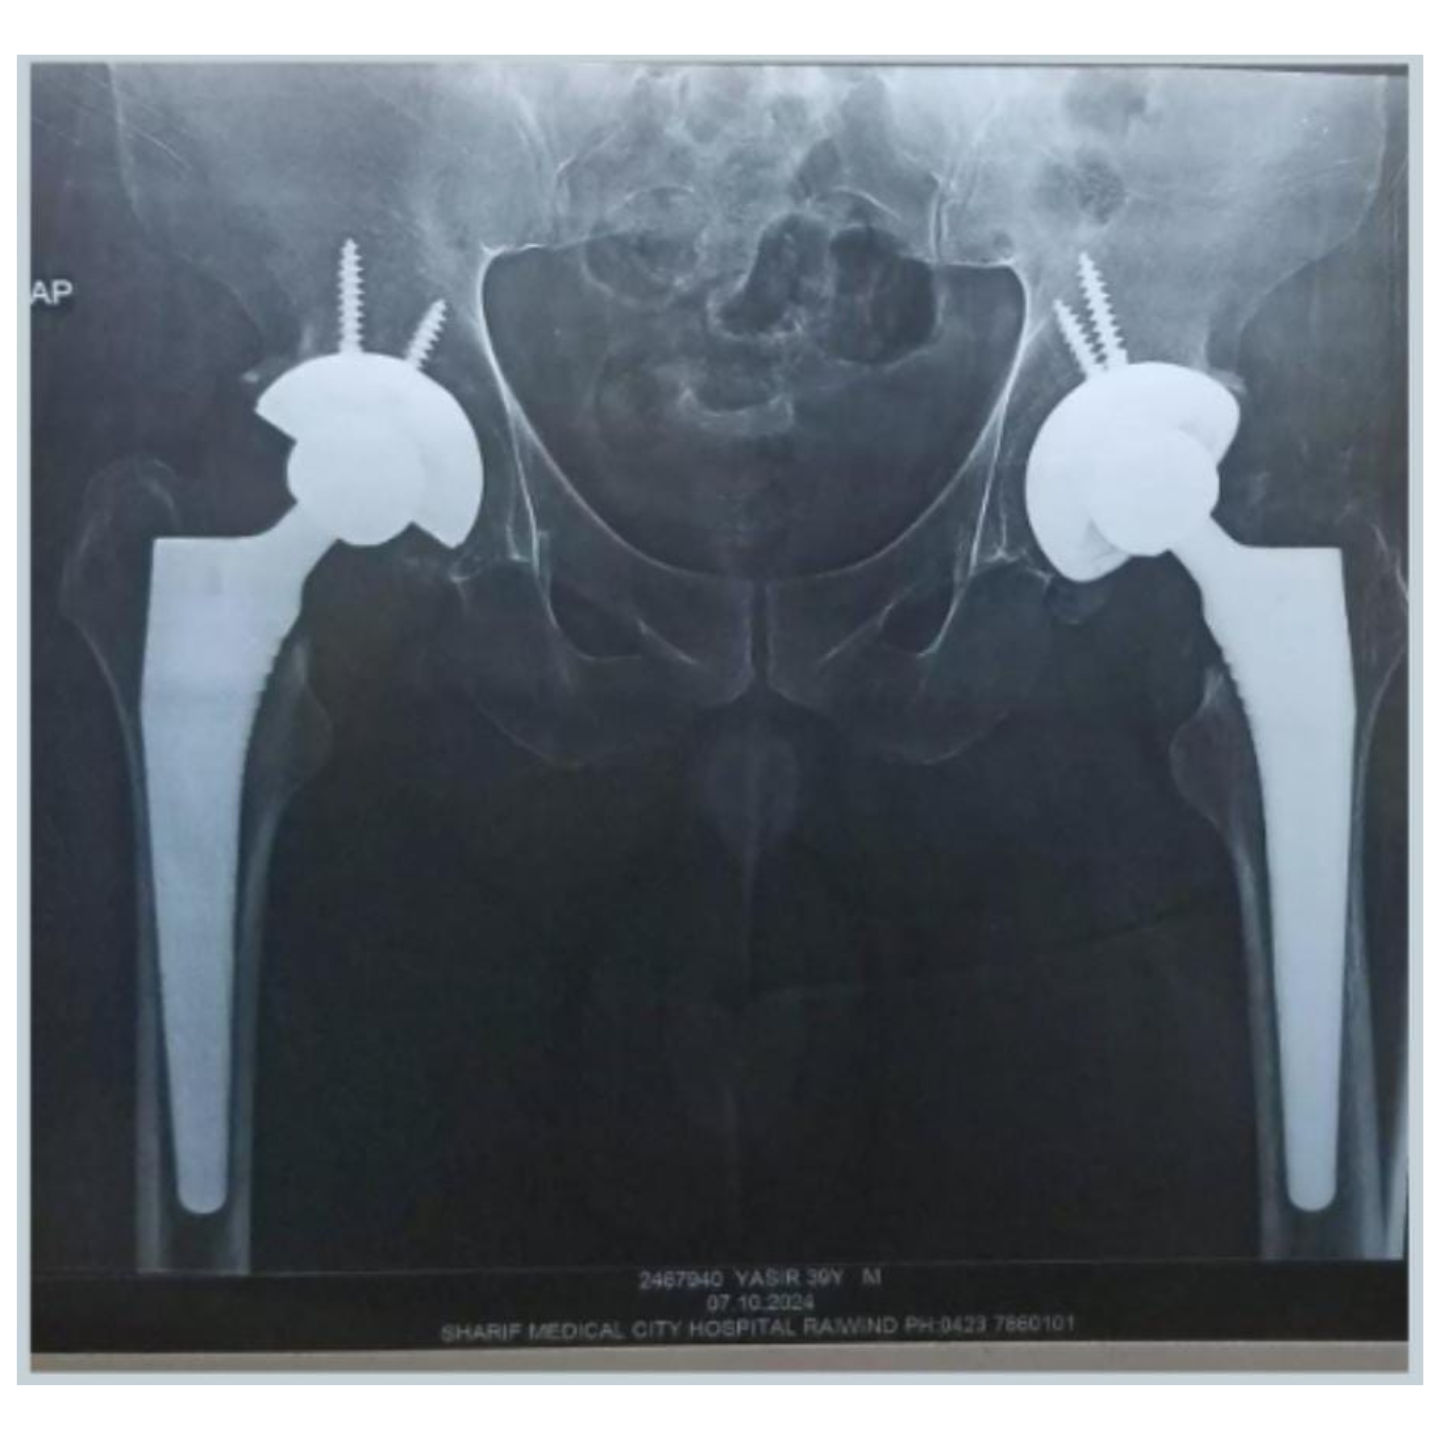

Bilateral total hip replacement surgery